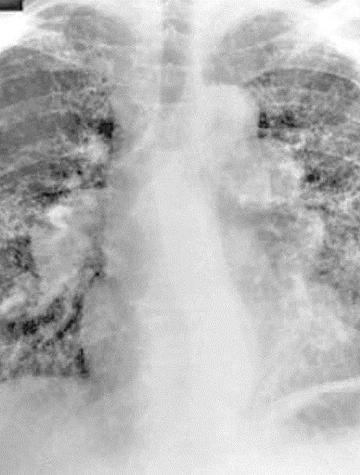

La sarcoïdose est une maladie multi-organique de cause inconnue caractérisée par une inflammation granulomateuse non nécrosante, touchant le plus souvent les poumons. La confirmation nécessite d’exclure d'autres affections, dont la bérylliose chronique qui ne peut être distinguée de la sarcoïdose sans tests spécifiques. Si la bérylliose chronique se développe principalement après inhalation de béryllium, la sensibilisation cutanée constitue un risque, et surtout, une [...]